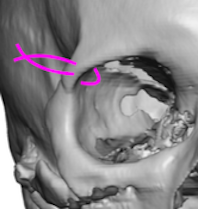

Infraorbital Implants

This procedure enhances the area below the eyes, targeting the infraorbital rim for improved contour and volume.Overview

A small incision is made either inside the lower eyelid (transconjunctival) or just under the lash line (subciliary).A custom or preformed implant is inserted along the infraorbital rim.

The implant is secured with screws or left in place depending on design and surgeon preference.

Pros:

Restores midface volume and reduces hollownessMinimally visible scarring when using internal incisions

Can improve tear trough appearance and support lower eyelid

Cons:

Swelling and bruising for 1–2 weeksRisk of implant shifting that may lead to loss of vision

Possible asymmetry

Requires precise planning for optimal contour and natural results

INFRAORBITAL IMPLANT BEFORE & AFTER

Price: €3,000–€8,000